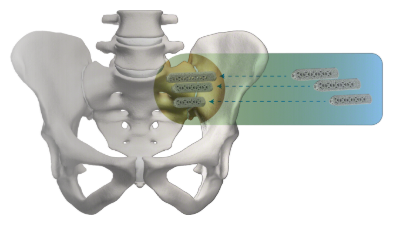

Once the SI joint is confirmed as the cause of your symptoms, treatment can begin. Some patients respond well to physical therapy, use of oral medications, or injection therapy. These treatments are often performed repetitively, and frequently symptom improvement using these therapies is temporary. If non-surgical treatment options have been tried and do not provide long-term relief, your surgeon may consider other options, including the minimally invasive iFuse procedure.

SI Joint Fusion with the iFuse Implant System®

Dr. John Orphanos is trained in the latest minimally invasive surgical (MIS) techniques, including use of the iFuse Implant System® from SI-BONE®, a medical device company pioneering MIS sacroiliac (SI) joint treatment. The iFuse Implant System is intended for sacroiliac joint fusion for some causes of SI joint pain. SI joint treatment using the patented triangular design of the iFuse implant has been clinically evaluated more than any other SI joint fusion procedure. More than 100, peer-reviewed publications demonstrate the safety, durable effectiveness, and biomechanical and economic benefits of the iFuse implant. The iFuse implant is the only SI joint fusion device with clinical studies, including two randomized controlled trials1,2, demonstrating that treatment improved pain, patient function, and quality of life.1-6 As with any minimally invasive surgical procedures, there are potential risks associated with the iFuse Implant System It may not be appropriate for all patients and all patients may not benefit. For information about the risks, visit www.si-bone.com/risks.

Indications

The iFuse Implant System® is intended for sacroiliac fusion for conditions including sacroiliac joint dysfunction that is a direct result of sacroiliac joint disruption and degenerative sacroiliitis. This includes conditions whose symptoms began during pregnancy or in the peripartum period and have persisted postpartum for more than 6 months. It is also intended for sacroiliac fusion to augment immobilization and stabilization of the sacroiliac joint in skeletally mature patients undergoing sacropelvic fixation as part of a lumbar or thoracolumbar fusion or for acute, non-acute, and non-traumatic fractures involving the sacroiliac joint. There are potential risks associated with the iFuse Implant System. It may not be appropriate for all patients and all patients may not benefit. For information about the risks, visit www.si-bone.com/risks.